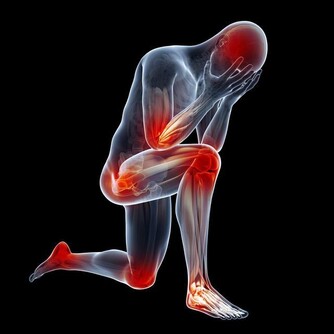

在痛風急性發作時,關節局部發熱、疼痛、紅腫,芹菜的上述功效正好派上用場,

因此芹菜很適合痛風急性期食用。